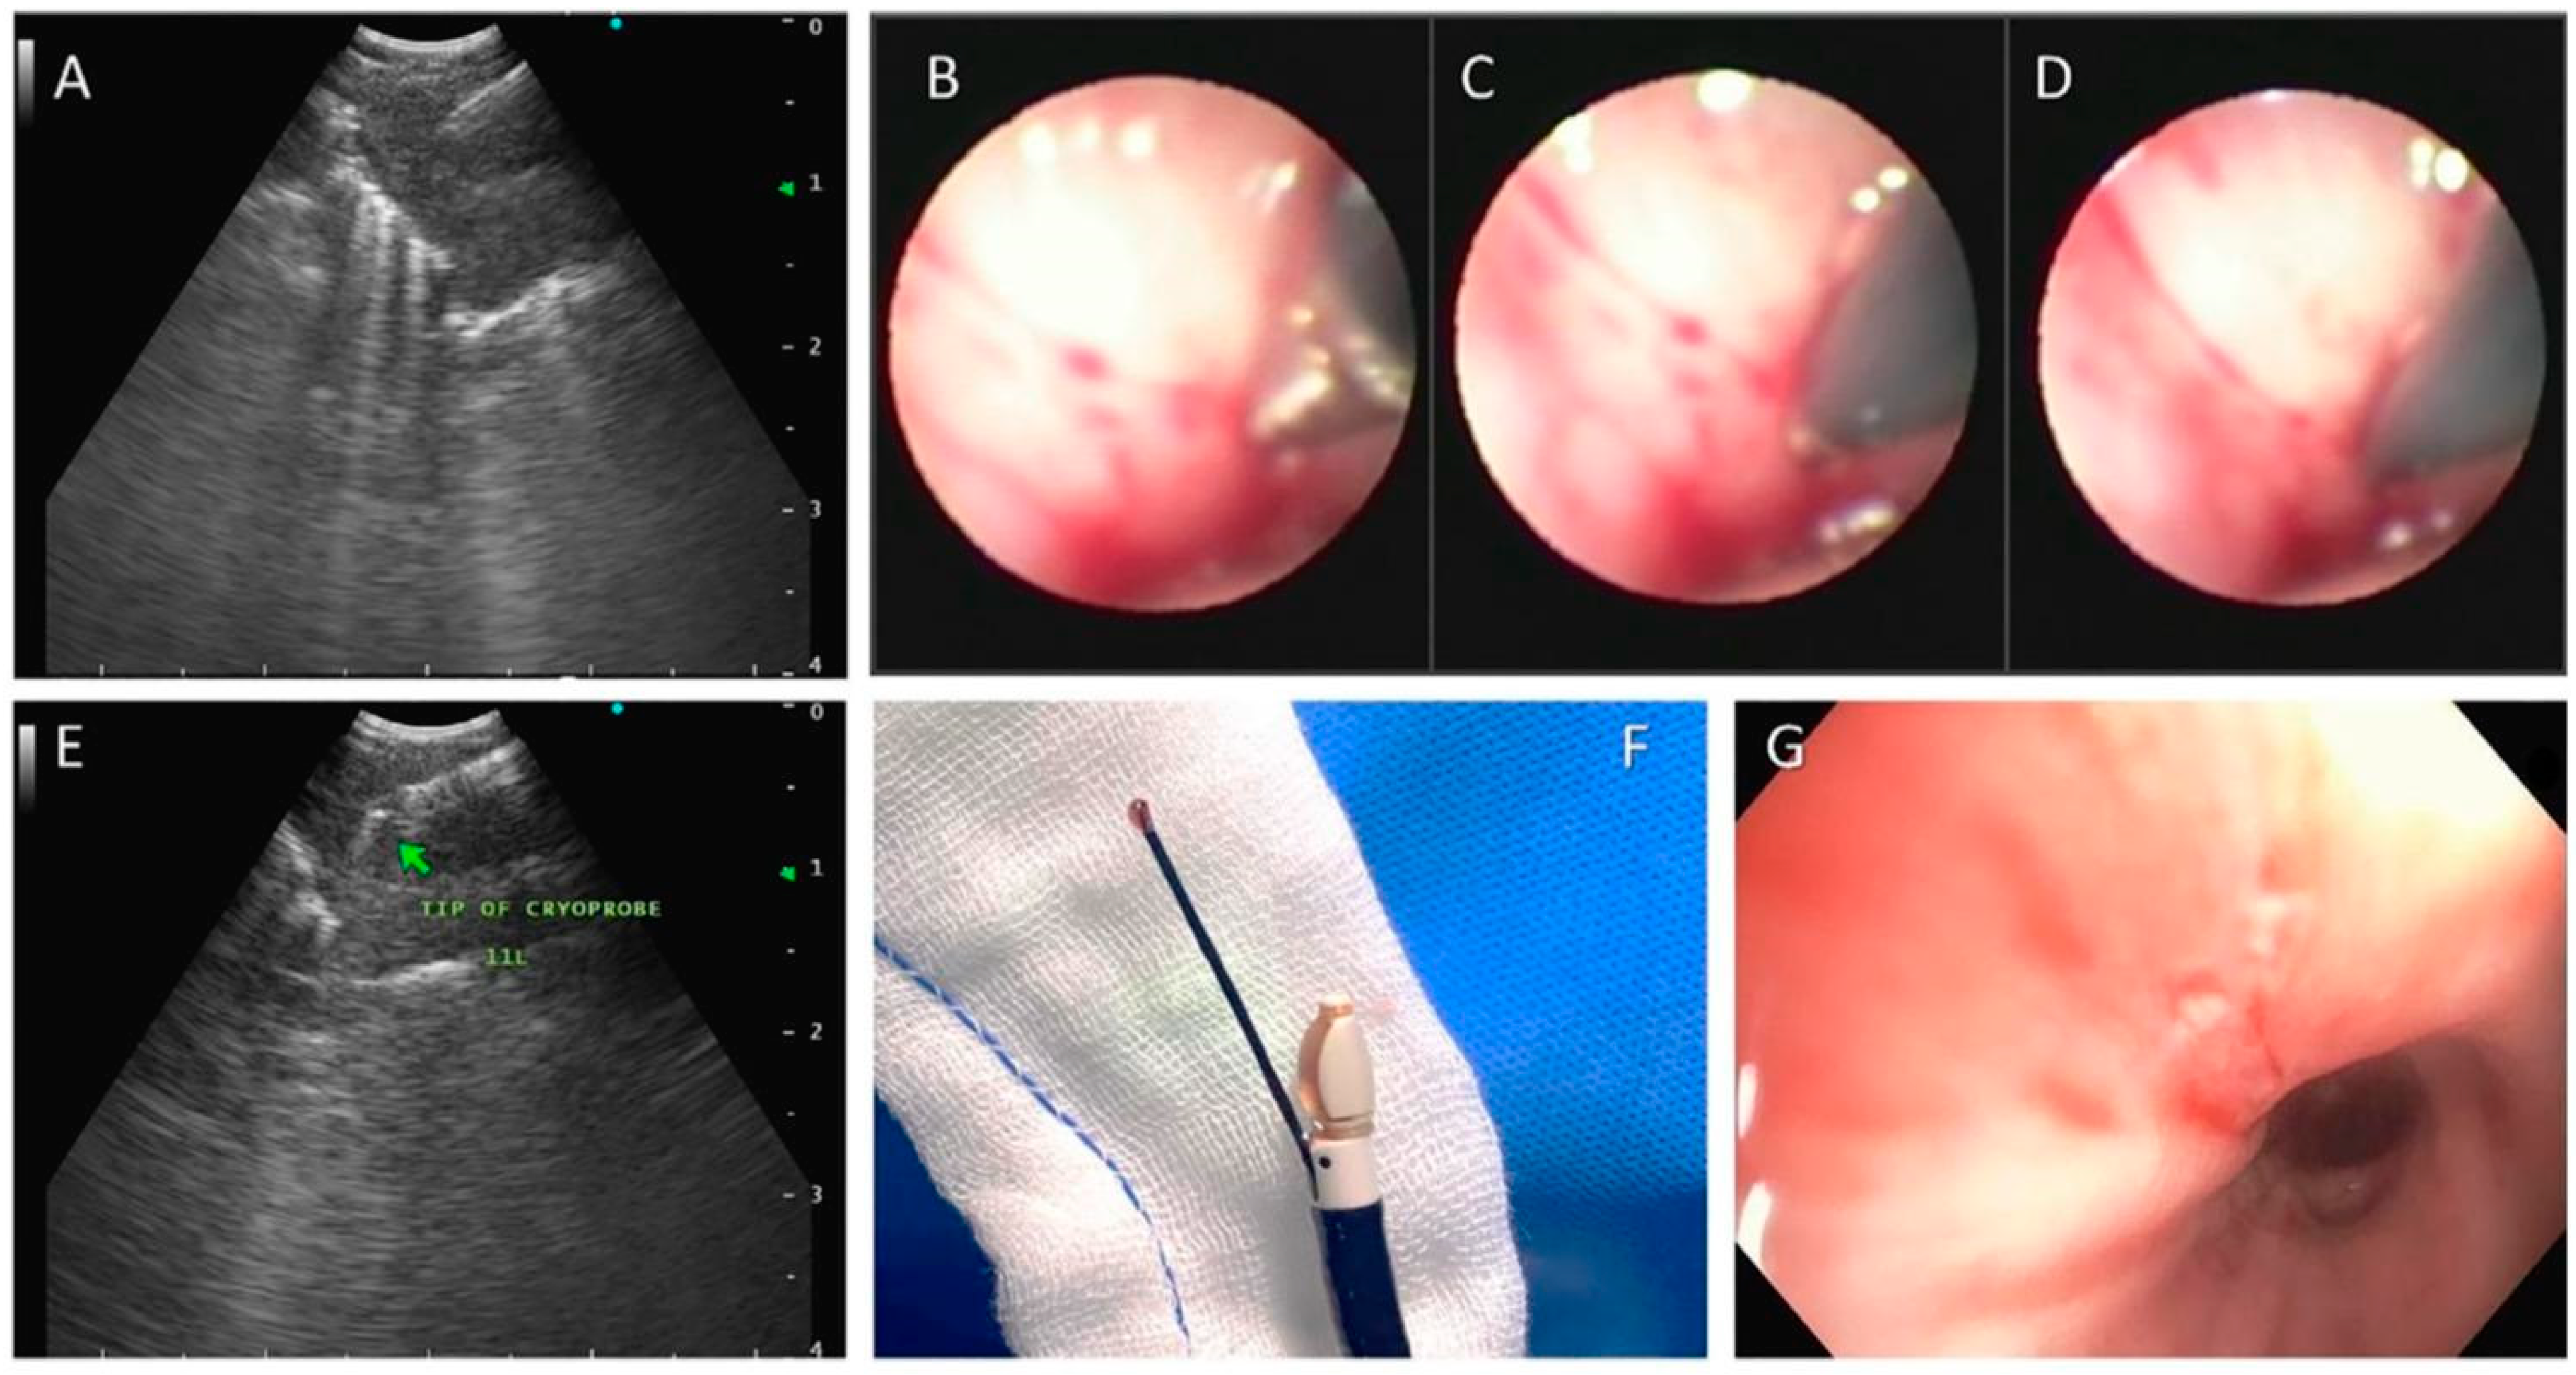

5. EBUS-Guided Transbronchial Cryobiopsy

- Gonuguntla, H.K.; Shah, M.; Gupta, N.; Agrawal, S.; Poletti, V.; Nacheli, G.C. Endobronchial ultrasound-guided transbronchial cryo-nodal biopsy: A novel approach for mediastinal lymph node sampling. Respirol. Case Rep. 2021, 9, e00808. [Google Scholar] [CrossRef] [PubMed] [PubMed Central]

- Ariza-Prota, M.A.; Pérez-Pallarés, J.; Fernández-Fernández, A.; López-González, F.; Cascón, J.A.; García-Alfonso, L.; Torres-Rivas, H.; Fernández-Fernández, L.; Sánchez, I.; Gil, M.; et al. Transbronchial Mediastinal Cryobiopsy in the Diagnosis of Mediastinal Lymph Nodes: A Case Series—How to do it. Arch. Bronconeumol. 2022, 58, 718–721. [Google Scholar] [CrossRef] [PubMed]